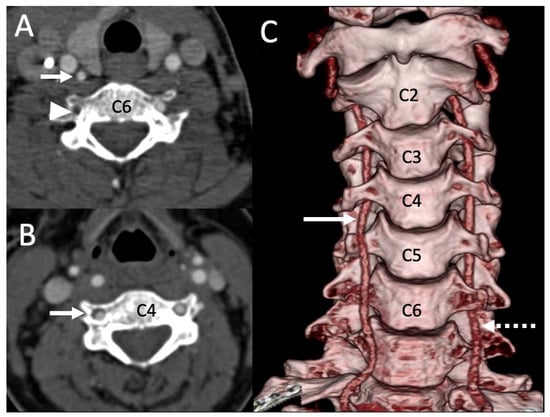

3.1. Variations in the V2 Segment